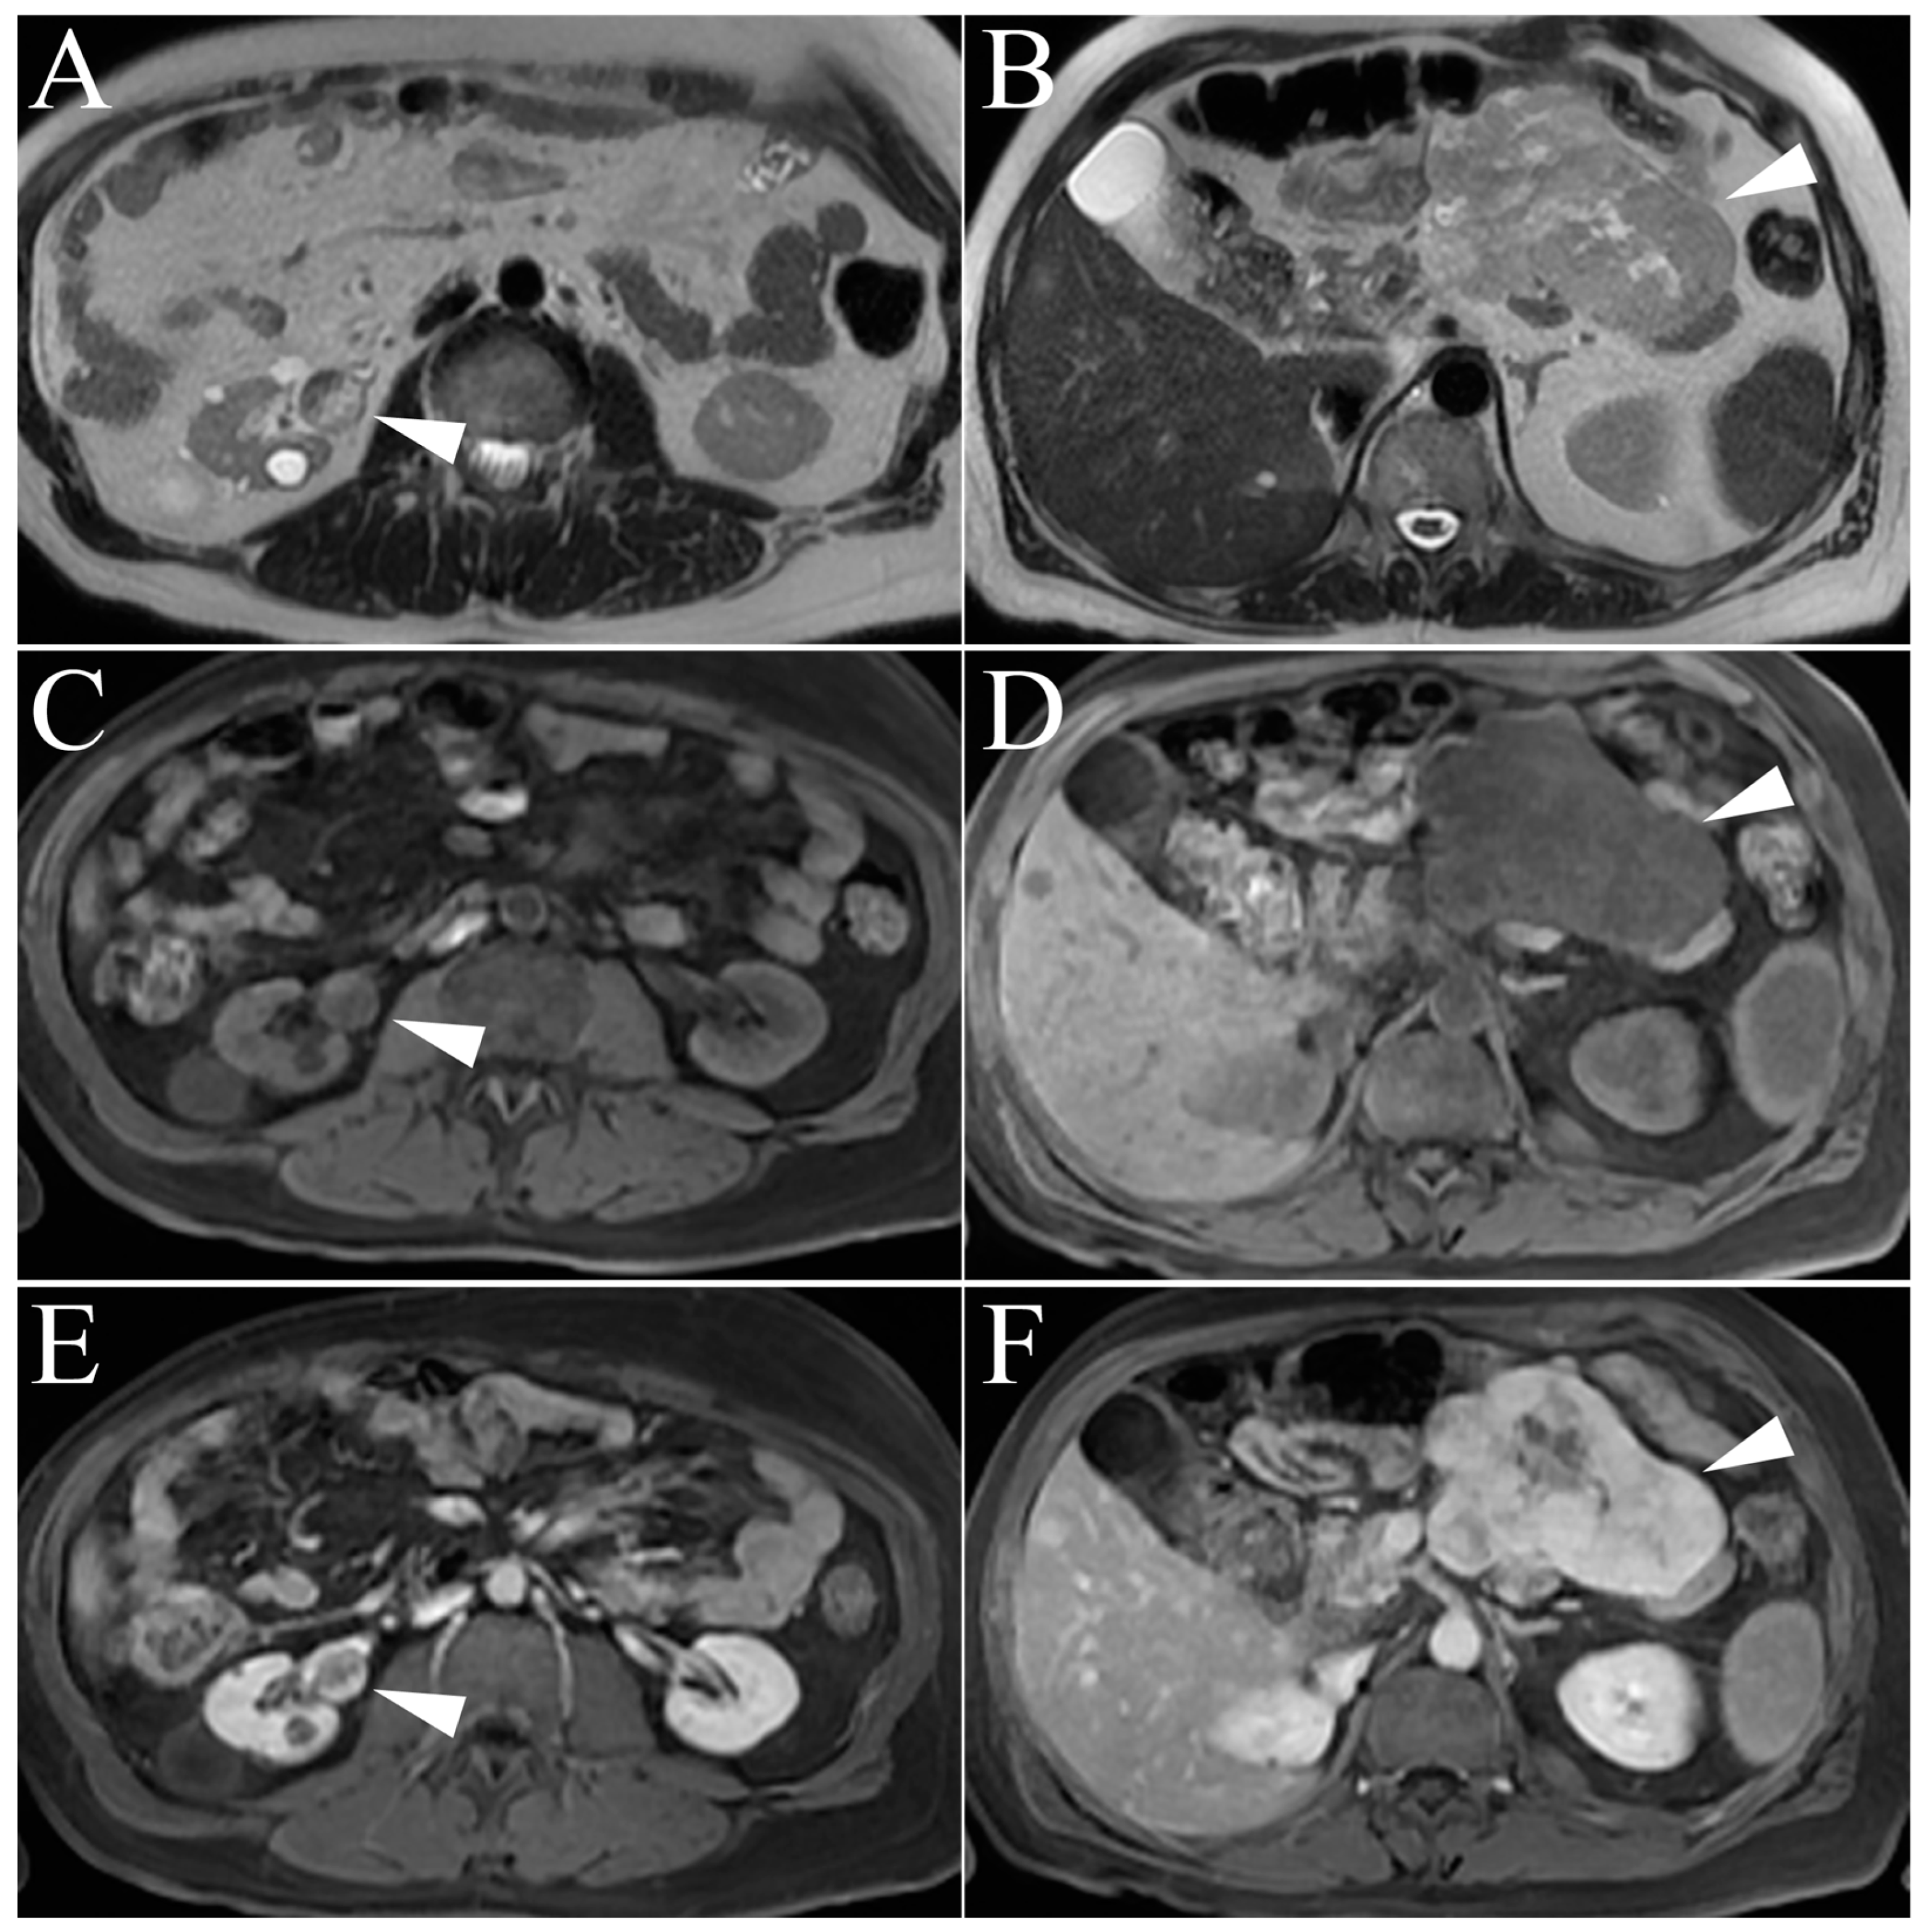

| Angiomyolipoma | High T2-intensity signal due to fat content. Low T2 on fat-suppressed images. Microscopic, intracytoplasmic fat made apparent with in- and out-of-phase GRE |

| Lipid-poor Angiomyolipoma | T2-hypointense Macroscopic fat and/or absence of fat High arterial enhancement with subsequent washout |

| Clear Cell RCC | Heterogenous, high T2-intensity Avid enhancement in corticomedullary and nephrogenic phases Microscopic fat as see on dual echo T1W in- and out-of-phase Invasion into surrounding vessels (esp. renal vein or IVC) Presence of necrosis or intralesional calcification |

| Chromophobe RCC | Low to intermediate T2-intensity Intermediate, delayed enhancement Central, stellate scar with “spoke-wheel” enhancement pattern Peripheral, homogenous, well-circumscribed Mimics oncocytoma on imaging |

| Metastasis | Varied presentation, usually identical to primary tumor Multiple, atypical renal masses History of advanced, non-renal malignancy |